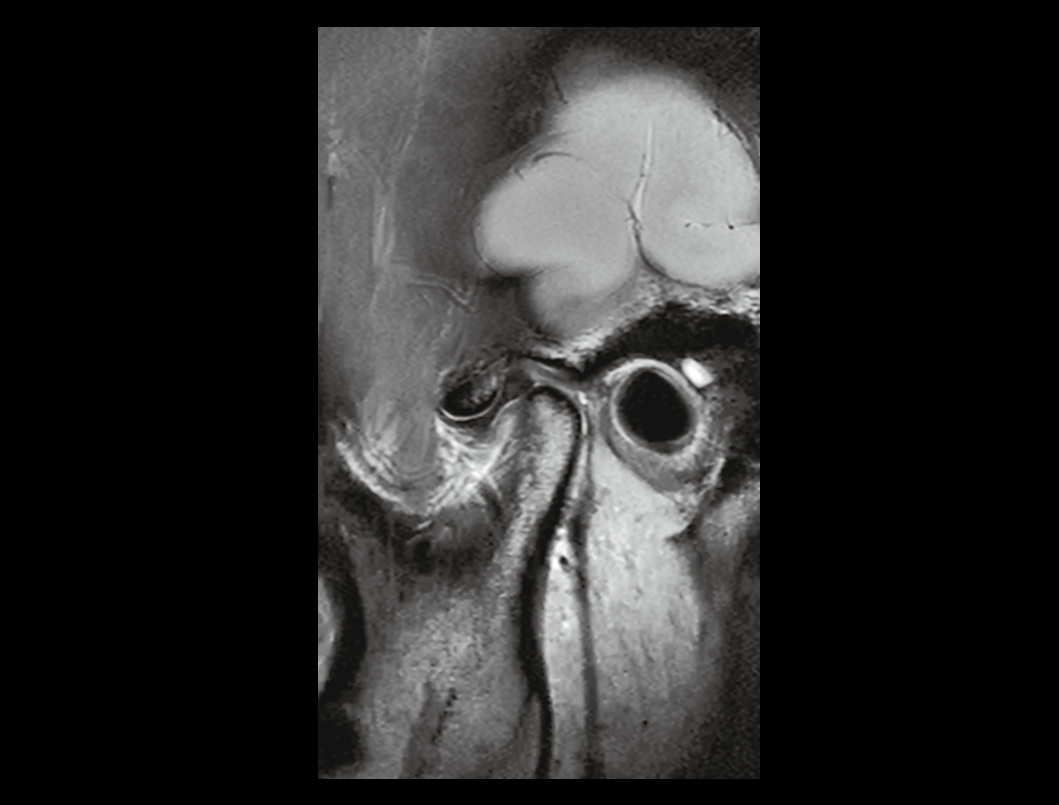

- Media